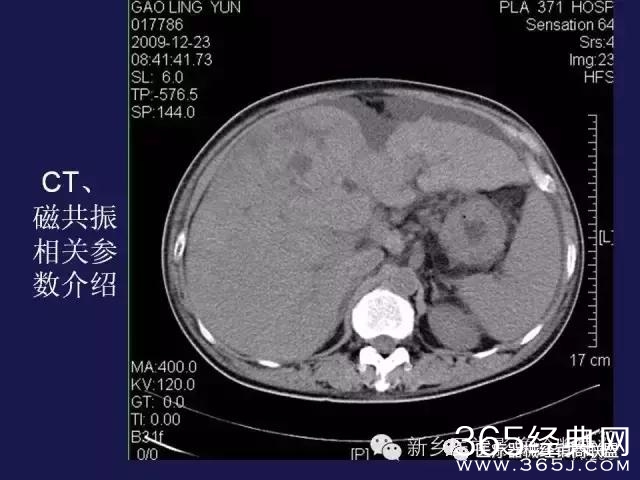

CT、MRI很难?NO,今日我们一起来学习一下如何读CT、MRI!

内行看门道: